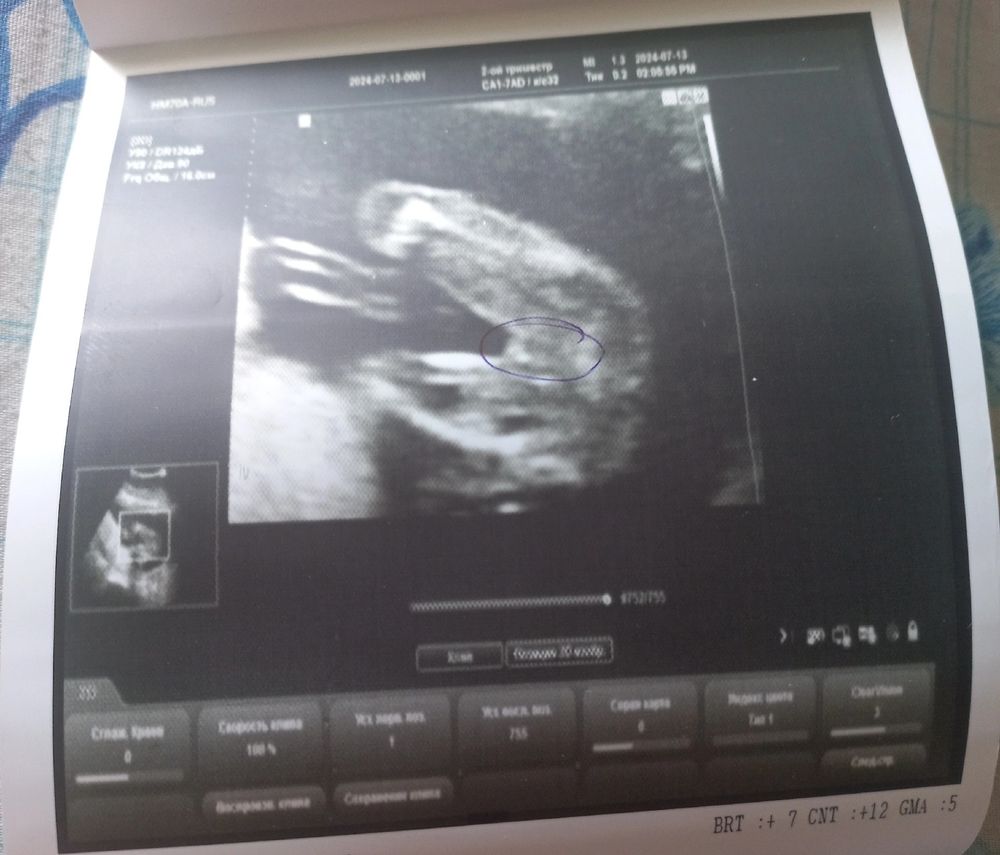

Точно ли девочка?

Девочка, по фото прям пирожок отчетливо видно😁у мальчиков все совсем не так там выглядит на узи)

УЗИ в 19.5, закрашиваю кружочек Когда можно узнать пол 👶🏻 ?